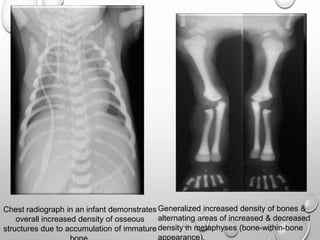

Chest radiograph in an infant demonstrates

overall increased density of osseous

structures due to accumulation of immature

Generalized increased density of bones &

alternating areas of increased & decreased

density in metaphyses (bone-within-bone

appearance).

Spine radiographs reveal classic sandwich vertebrae of osteopetrosis (red

arrows). This is manifested as thickening and sclerosis of the vertebral endplates,

and of the bone adjacent to the endplates.

There is also marked thickening of the posterior vertebrae (yellow arrows),

especially in the vertebral arch.